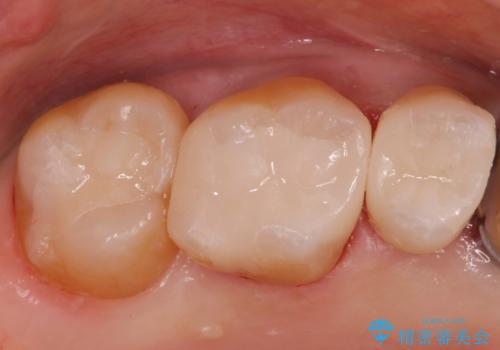

[ 歯肉縁下齲蝕 ] 歯周外科を行った虫歯治療

黒くなった奥歯をジルコニアクラウンに